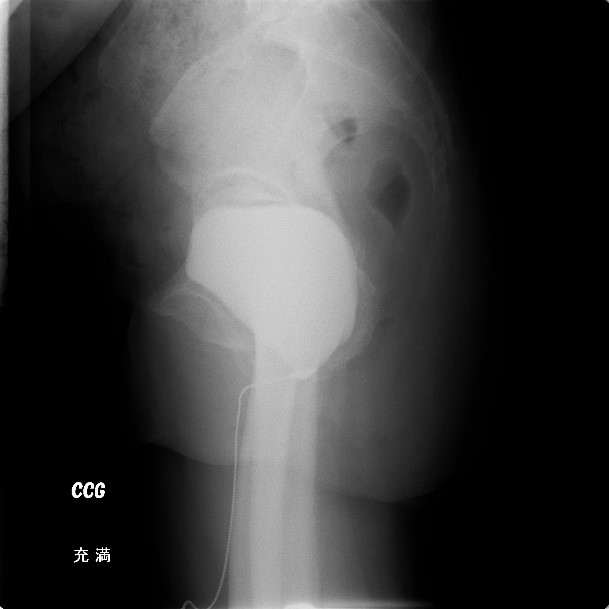

■ チエーンCG

膀胱の形状や尿道との位置関係を調べ、主に腹圧性尿失禁や子宮・膀胱などの骨盤臓器脱の診断に用いる検査です。